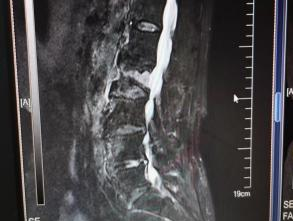

多年来,贵州航天医院各科室紧跟医学前沿,不断强技术、补短板,大力开展新技术、新项目,完成了许多高精尖、高难度、本地区“首例”的技术,填补了医院医疗技术空白,满足了群众日益增长的医疗需求。 贵州航天医院骨科率先在遵义地区开展骨搬移技术,截至目前,已治愈慢性骨髓炎、感染性骨不连、骨缺损、脉管炎、糖尿病足患者200余例,糖尿病足治疗保肢率达到98%。 本期,我们将为大家带来骨科特色技术——骨搬移技术(Ilizarov)。 案例分享 一名59岁的患者,身患糖尿病12年,在来我院3个月前出现了右脚溃烂的症状,来院就诊时,患者的右脚十分红肿,右脚脚趾坏死,伤口处不断流出黑红色脓液,情况十分严重。在接诊到患者时,骨科专家团队高度重视,立刻为患者完善了CT血管造影(CTA)等相关检查,诊断为:2型糖尿病,糖尿病周围血管病变,右糖尿病足。 术 前 考虑到患者情况比较严重,为最大限度保证患者肢体完整,科室专家团队进行了严格的讨论评估,为患者制定了骨搬移技术治疗方案,在征得患者及其家属的同意后,成功通过搬移骨块为患者进行治疗,促进患者病变肢体血管再生。 胫骨横向骨搬移外架固定 清除感染病灶 术后调节外架,通过搬移骨块 促进患肢血管再生 患者在术后三周前来换药,观察到感染得到进一步控制;术后六周复查,患者病变处已愈合,进行CT血管造影(CTA)后可明显观察到足部血管再生。 术后3周 术后6周愈合 CT血管造影见足部血管再生 糖尿病患者全身与局部的问题互为影响,形成恶性循环,糖尿病足溃疡创面迁延不愈,常见干性坏疽、湿性坏疽、趾坏死、深且大的溃疡以及骨髓炎等症状,还可导致脓毒血症,以往为保全生命,患者被迫选择一次或多次截肢。骨搬移技术的发展进步,能在血糖有效控制、局部有效清创下,有效促进患肢微血管再生,改善患肢血供,达到糖尿病足更快治疗康复的目的,并能根据病变情况最大限度的保障患者肢体完整。 什么是骨搬移技术 骨搬移技术是通过使用专用的骨外固定器固定骨段,每天缓慢牵拉,在牵拉搬移过程中,骨段尾部形成新骨及新的软组织,从而修复骨骼缺损及软组织缺损。是治疗大段骨缺损、骨不连、骨感染、肢体畸形的金标准方法,也用于治疗脉管炎、糖尿病足等肢体缺血性疾病。 骨感染缺损 切除感染段 搬移骨段 新骨形成 骨感染根治愈合 骨搬移技术原理 生物组织在持续、稳定、缓慢牵拉下,能刺激细胞分裂、组织再生,骨外固定技术运用该原理,通过持续缓慢调节外固定器形成牵拉张力,促进牵引成骨与相邻组织再生,如神经、血管、肌肉、皮肤等再生,达到治疗大段骨缺损、肢体缺血如糖尿病足等疾病的目的。 骨搬移技术优势 (一)除治疗骨缺损、骨不连外,有更广的适用范围,利用组织再生、血管再生等特性,能大量运用于肢体畸形的矫形、糖尿病足等的治疗。 (二)治疗效果确切,重建肢体外型和功能,极大降低截肢率和残疾率。 (三)明显提高了患者生活质量,极大减轻其家庭及社会负担。 肢体畸形的矫形 慢性骨髓炎 骨段切除 术后1年 濒临截肢的脉管炎术后6周 难愈创面术后3周 贵州航天医院骨科 专家团队 赵学平 骨科主任 主任医师 临床擅长:从事骨科临床工作30余年,对骨科常见疾病的诊治具有丰富的临床经验。 世界中医药联合会脊柱康复专业委员会常务理事,中华中医药学会整脊分会常务委员,中国中西医结合学会骨伤科分会肢体矫形功能重建与康复专家委员会常务委员,中国研究性医院学会骨科创新与转换专业委员会关节外科学组保髋工作委员会常委,中国康复技术转化及发展促进会骨外科与康复技术转化专业委员会常务委员,泛珠三角区域运动医学联盟(PPRD-SMA)理事会常务理事,中国研究型医院学会运动医学专业委员会委员,贵州省中医药学会整脊分会副主任委员,贵州省中西医结合学会银质针专业委员会副主任委员,贵州省康复医学会骨与关节专业委员会常务委员,贵州省人民医院骨科专科联盟常务理事,贵州省康复医学会骨内科专业委员会常务委员,中华医学会贵州省骨科学会委员,贵州省康复医学会脊柱脊髓专业委员会常务委员,贵州省运动医学分会委员,贵州省康复医学会骨与软组织肿瘤专业委员会委员,遵义市医学会创伤分会副主任委员,贵州省康复医学会骨内科专业委员会遵义地区分会常务委员,遵义市医疗事故鉴定、伤残鉴定、工伤鉴定、司法鉴定专家。 长期从事骨科临床研究及教学工作,在国家级、省部级杂志发表论文20余篇,SCI论文2篇,参与主编骨科专著2部,主持省部级科研项目2项,参与指导省部级、市级科研项目6项。 陈明勇 骨科副主任 副主任医师 临床擅长:从事创伤骨科工作约20年,对骨缺损、骨不连、骨肿瘤、肢体畸形等的肢体矫形重建及功能重建,慢性化脓性骨髓炎的根治治疗、糖尿病足的保肢治疗、快速康复理念(ERAS)下的老年骨折的诊治,四肢复杂骨折的诊治,四肢骨折等微创手术治疗具有丰富的临床经验。 2004年毕业于遵义医学院临床专业,曾在中国人民解放军总医院、广西医科大学第一附属医院、上海第六人民医院骨科进修。中国中西医结合学会骨伤科专业委员会横向骨搬移治疗糖尿病足及微血管网再生学组首届委员,遵义市医学会创伤分会常务委员。 瞿 辉 骨科 副主任医师 临床擅长:对骨科的常见病、关节外科、脊柱外科及运动医学疾病的诊治具有丰富的临床经验,熟练掌握骨科手术操作技术。 毕业于遵义医学院临床医学系,2005年前往广州中山大学第一附院骨显微医学部进修学习,2011年前往成都华西医院进修学习,并多次在省内外学习骨科相关知识,是中华医学会骨科分会会员。 赵兴东 骨科 主任医师 临床擅长:擅长骨科的常见病及各种创伤、四肢骨折创伤修复、骨感染、手足疾病的诊治和手足体表畸形的矫形整复,熟练掌握骨科四肢骨病及创伤的手术操作技术,尤其在四肢关节复杂性损伤、手足外伤、组织缺损创面、难治创面的皮瓣修复方面及平足、高弓足矫形方面及四肢慢性疼痛诊治、康复方面具有丰富的临床经验。 硕士研究生,毕业于遵义医学院临床外科系,2015年前往山东省立医院手足外科进修学习;遵义市医学分会创伤分会第一、二届委员,遵义市手外科医学会第二委届员会常务委员;在省级及省级以上期刊发表文章9篇,参编著作2部,参与主持并完成市级课题1项,参与市级课题2项、省级课题1项。 张俊凯 骨科 副主任医师 临床擅长:从事骨科临床工作28年,对创伤骨折、骨感染、骨缺损、骨不连等外科诊治,四肢骨折的微创手术治疗,四肢复杂骨折(如关节内粉碎性骨折、多发骨折等)的损伤控制及手术治疗等具有丰富的临床经验。 1995年毕业于遵义医学院临床专业,2009年前往复旦大学附属医院骨科进修1年。 卢懿明 骨科 副主任医师 临床擅长:从事骨科工作18年,对创伤骨折、四肢骨折的微创手术治疗、四肢复杂骨折(如关节内粉碎性骨折、多发骨折等)的损伤控制及手术治疗,尤其是髋部骨折的PFNA等微创技术,踝关节骨折、膝关节周围骨折的Mipo微创技术等具有丰富的临床经验,开展了4项新技术,发明6项新型专利技术。 2005年毕业于遵义医学院临床专业,2017年,前往南方医科大学第三附属医院骨科进修半年,回院后运用Mipo技术对骨干骨折及干骺端骨折的治疗技术,同时积极开展骨盆骨折、髋臼骨折腹直肌外侧切口的应用;发表了多篇专业论文,经常参与省内外学术交流会授课,获得医院荣誉称号多个。 邬夏荣 骨科 副主任医师 临床擅长:从事骨科工作16年,对四肢复杂骨折、骨肿瘤的诊治,尤其是足踝创伤、慢性踝关节损伤、平足症等诊疗具有丰富的临床经验。 2006年毕业于遵义医科大学临床医学专业,曾在陆军军医大学西南医院进修学习,发表多篇骨科学术论文。 余德怀 骨科 副主任医师 临床擅长:从事骨科工作10余年,对运动医学、骨关节、脊柱外科常见病、多发病的诊治具有丰富的临床经验。 硕士研究生,2011年毕业于遵义医学院临床医学专业,曾前往遵义医科大学附属医院运动医学专业进修学习;是贵州省医学会运动医学分会青年委员,西部关节镜联盟委员;发表多篇骨科学术论文。 冯 乾 骨科 副主任医师 临床擅长:从事骨科工作近20年,熟练掌握骨科多发病及常见病的诊治,尤其对脊柱退变性疾病的诊断及治疗具有丰富的临床经验,主要研究脊柱微创相关治疗方式,能熟练开展椎间孔镜及VBE。 曾前往北京大学第三医院进修学习疼痛及椎间孔镜、首都医科大学友谊医院专业进修脊柱内镜;是贵州省康复医学会第三届脊柱脊髓专业委员会委员;发明专利3项、发表脊柱外科专业论文多篇。 张艳金 骨科 副主任医师 临床擅长:从事骨外科工作16年,对复合伤、多发伤的救治、四肢骨干骨折、关节周围骨折、骨肿瘤、骨髓炎等诊治具有丰富的临床经验。 中共党员,硕士研究生,2006年本科毕业于山西医科大学第二临床医学院,2011年研究生毕业于北京军区总医院;在“老年COPD患者合并髋部骨折的诊治”国际合作课题组研究两年,在老年髋部骨折的诊治方面具有丰富的经验,并发表论文6篇;承担遵义市级课题1项;承担遵义医科大学的临床教学工作,获得遵义医科大学优秀带教老师荣誉。编撰有《骨科疾病诊疗精粹》一书,开展2项新技术,编撰地方规范《务川自治县创伤骨科常见疾病诊疗规范》一书。 赵小锋 骨科 副主任医师 临床擅长:从事骨科临床工作11年,对骨科常见病、多发病诊疗有较为丰富的临床经验,擅长脊柱相关疾病诊断及治疗,尤其是颈、腰、腿疼痛疾病诊断及治疗,擅长胸腰椎骨折微创经皮穿刺内固定术、经皮穿刺椎体成形术、经皮穿刺脊柱内镜下腰椎间盘摘除术、单纯开创腰椎间盘摘除术、腰椎滑脱复位椎间植骨椎融合内固定术、腰椎管狭窄减压融合内固定术及人工髋、膝关节置换术等。 2012年毕业于遵义医学院外科学专业硕士研究生,2019年参加“遵义市115医学人才精英计划”于上海交通大学第一附属医院培训学习,2023年于北京大学第三人民医院脊柱外科进修学习,曾获得遵义市优秀医师荣誉称号。 遵义市手外科第一届委员,遵义市医学会创伤分会第一届委员,遵义市医学会创伤分会第二届委员,贵州省康复医学会第三届脊柱脊髓专业会委员,遵义市医学会烧伤与整形外科学分会委员,发表论文5篇,其中国家级核心期刊1篇,SCI论文1篇,主持市级课题1项并结题,参与市级课题2项。 贵州航天医院骨科简介 基本情况 贵州航天医院(原3417医院)骨科组建于1968年,前身是以创伤和断肢(断指)再植闻名于世的上海市第六人民医院骨科,中国断肢(断指)再植的奠基者、中科院院士陈仲伟等著名专家、学者多次莅临科室指导医疗、教,是贵州省最早拥有专业骨科技术科室之一,在70年代开展了贵州省首例断肢(断指)再植手术。组建50余年来,诊治患者已逾百万,挽救了无数的伤病员,成为了保障遵义地区人民群众健康的重要支撑。 经过几代人的不懈努力,今天的骨科,已由创伤骨科发展至骨病、骨肿瘤、骨结核等领域,现有脊柱外科、关节外科、四肢创伤、手足外科四个亚专科,成为了集医疗、教学、科研于一体的综合学科,是贵州省临床重点专科、遵义市临床重点专科、遵义市骨科临床医学中心、遵义市基层骨科专科联盟理事长单位。 科室目前开放床位110张,共有医护人员50余人,副高级以上专家18人,硕士研究生15人。拥有一流骨科医疗设备多台,每年不定期选派优秀技术骨干到全国各大知名医学院校进修、学习、参观、交流,并邀请国内、国外知名专家教授来院进行交流、指导,通过不断引进国内外先进的诊疗技术,科室医疗技术水平稳步提升,为广大人民群众提供了优质的医疗服务。 专科特色 骨一科 (一)骨缺损、骨不连的肢体与功能重建 胫骨横向骨搬移技术治疗糖尿病足: (二)慢性骨髓炎的根治治疗 (三)肢体缺血性疾病如糖尿病足、脉管炎的保肢治疗 (四)皮瓣修复 (五)复杂创伤的治疗 (六)老年髋部骨折及小儿骨折快速手术 老年髋部骨折: 骨二科 (一)胸腰椎骨折微创经皮椎弓根螺钉固定术 (二)老年性骨质疏松性患者腰椎滑脱脊柱内固定术(骨水泥螺钉) (三)V形双通道脊柱内镜技术(VBE)腰椎融合术治疗腰椎退行性疾病 (四)老年性骨质疏松性骨折(PVP/PKP)术 (五)人工髋关节置换术 (六)双侧股骨头坏死人工全髋关节置换 (七)右侧全髋置换术后假体周围骨折翻修 (八)人工膝关节置换术 (九)人工膝关节假体松动翻修 (十)关节镜技术 传统手术切口 关节镜技术切口 诊疗范围 骨一科 1.四肢创伤、矫形。 2.手、足踝外科。 骨二科